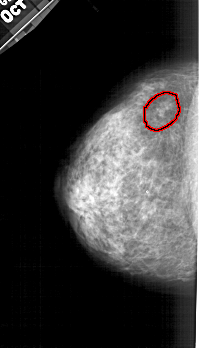

A_1427_1.RIGHT_CC

RIGHT_CC LINES 4666 PIXELS_PER_LINE 2746 BITS_PER_PIXEL 12 RESOLUTION 43.5 NON_OVERLAY

FILE: A_1427_1.LEFT_MLO.OVERLAY

TOTAL_ABNORMALITIES 1

ABNORMALITY 1

LESION_TYPE CALCIFICATION TYPE AMORPHOUS DISTRIBUTION CLUSTERED

ASSESSMENT 4

SUBTLETY 3

PATHOLOGY BENIGN

TOTAL_OUTLINES 1